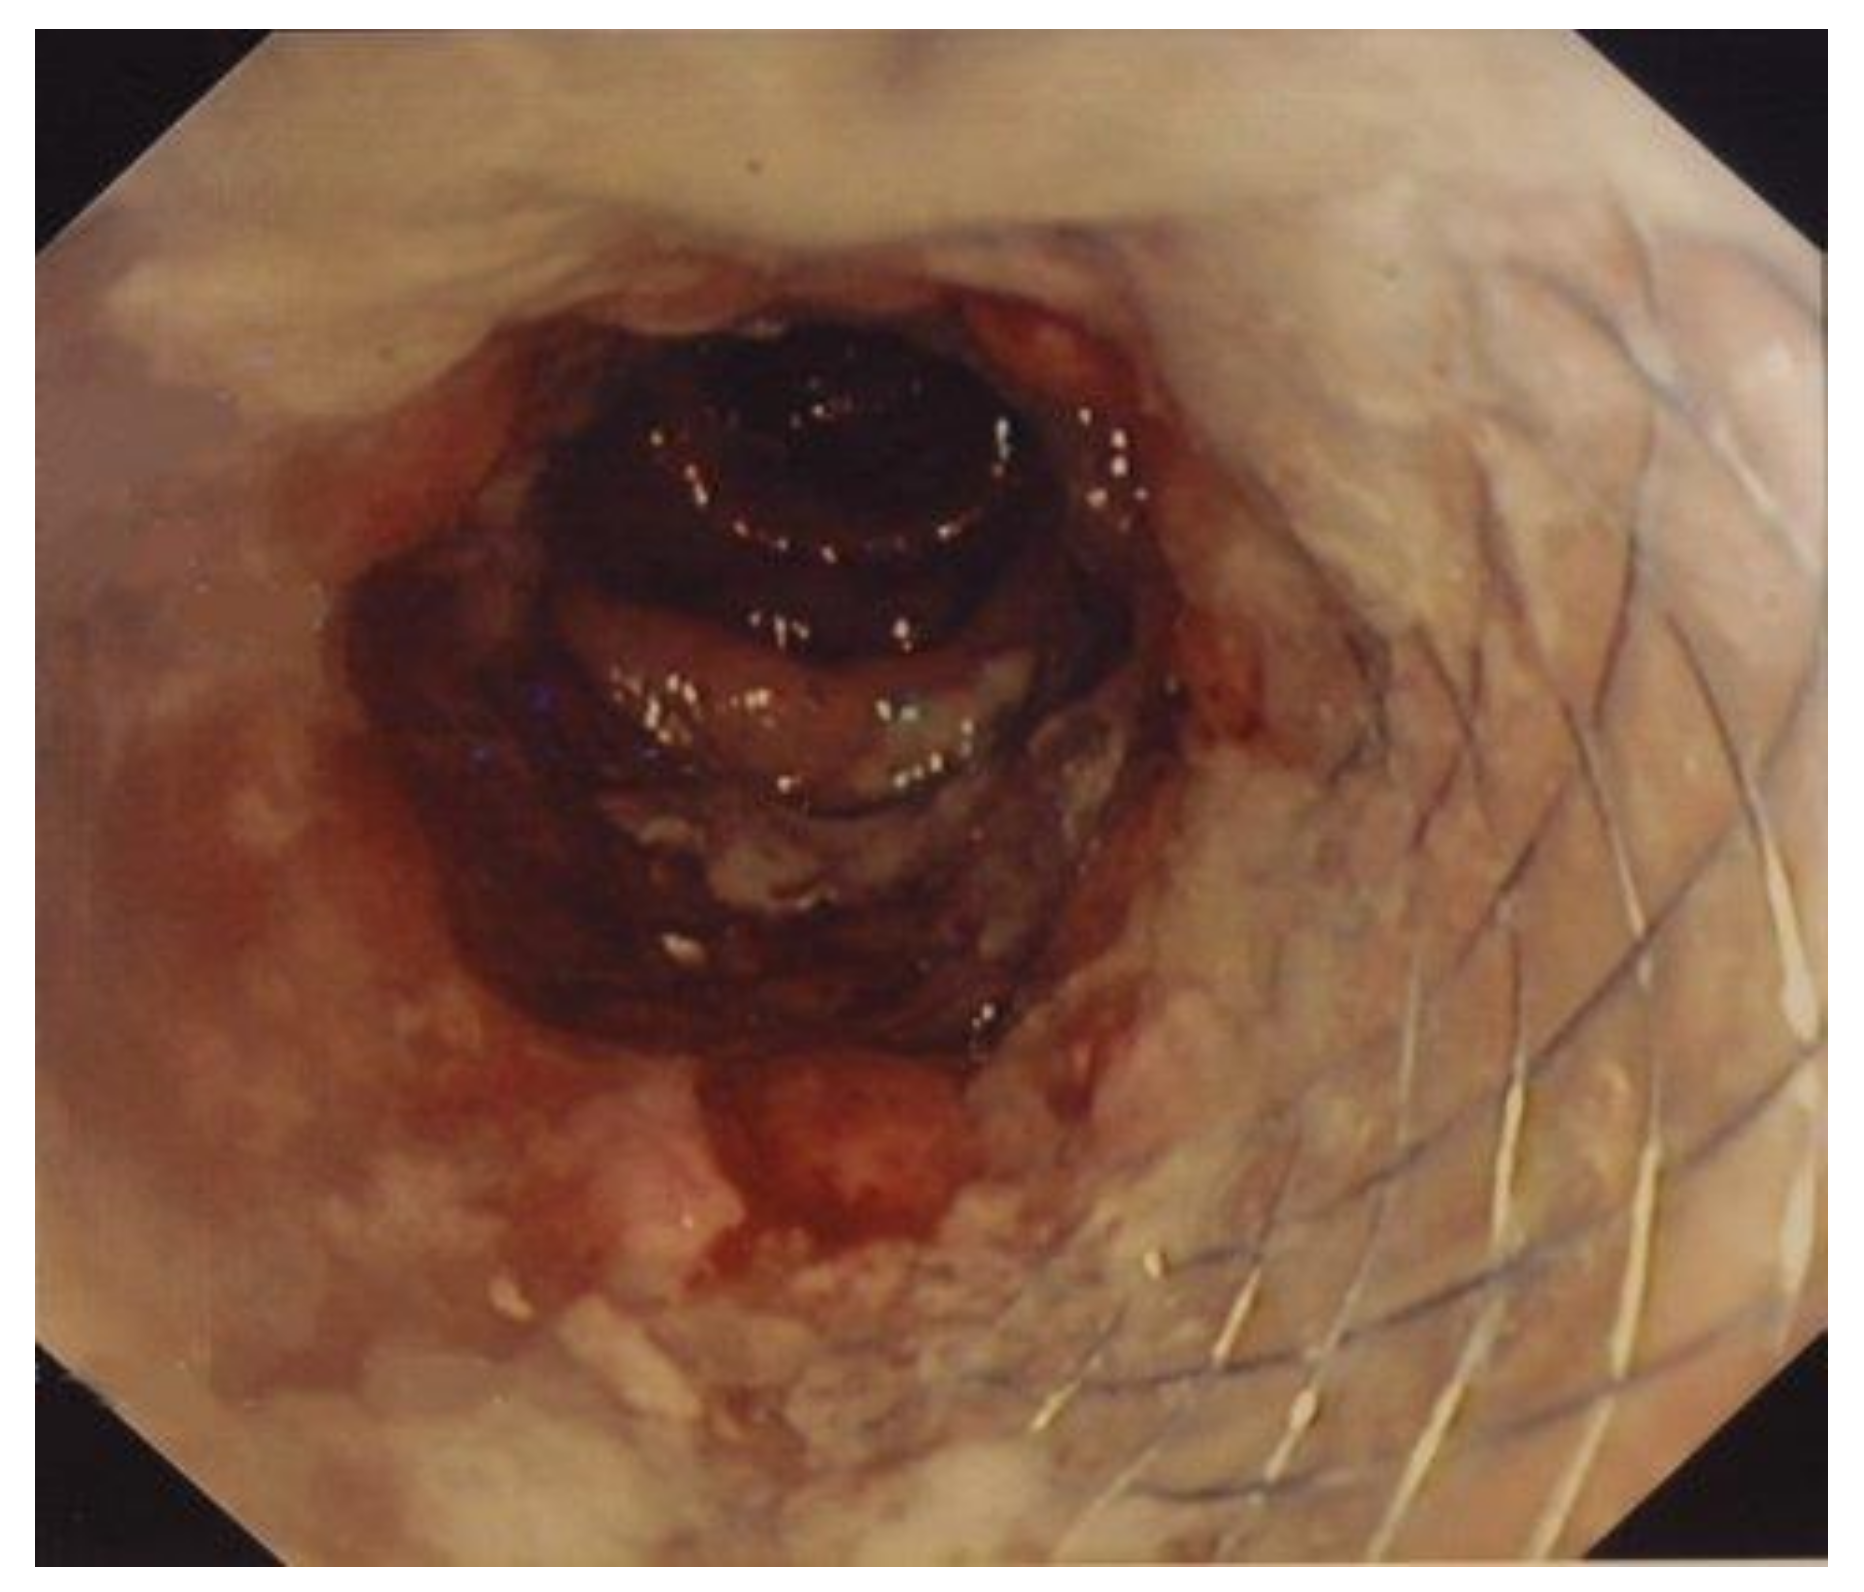

2.3. SEMS Placement